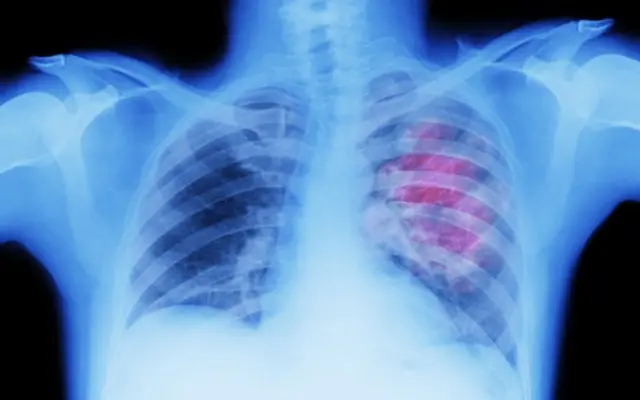

Coughing up blood fit be a sign of lung cancer.

Continuous cough fit be sign of lung cancer.